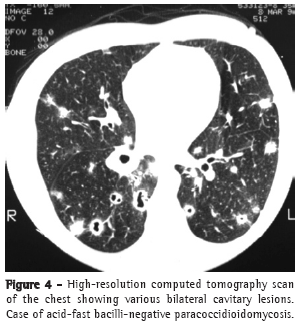

In most cases, the clinical complaints, the physical examination data, and the radiological alterations presented by these patients did not allow a clear distinction to be made between the two diseases in most cases (Figures 2-4).

The majority of individuals with PCM are male (15:1) and are farm laborers or former farm laborers between 30 and 50 years of age. Although such individuals are often oligosymptomatic, with few physical examination findings, they can present pronounced alterations on simple chest X-rays and on high-resolution computed tomography scans of the chest.(11-15)

Pulmonary alterations are typically bilateral, predominantly in the middle lobes and spinal cord regions.(16,17)